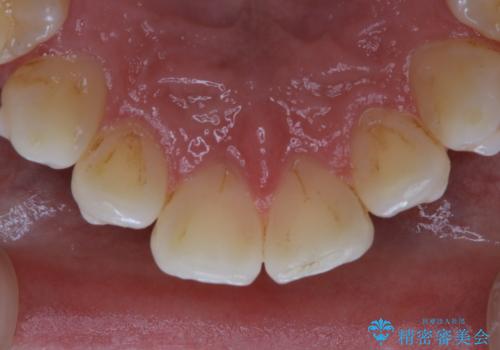

- インビザライン矯正治療中の方です。アタッチメントの周りの汚れが気になるとのことで、PMTC30分コースを行いました。

インビザライン矯正治療はマウスピースを長時間使用するため、歯石や汚れなどが付着したままだと、フィットが悪くなったり、口臭が強く出たりする原因につながることもあります。